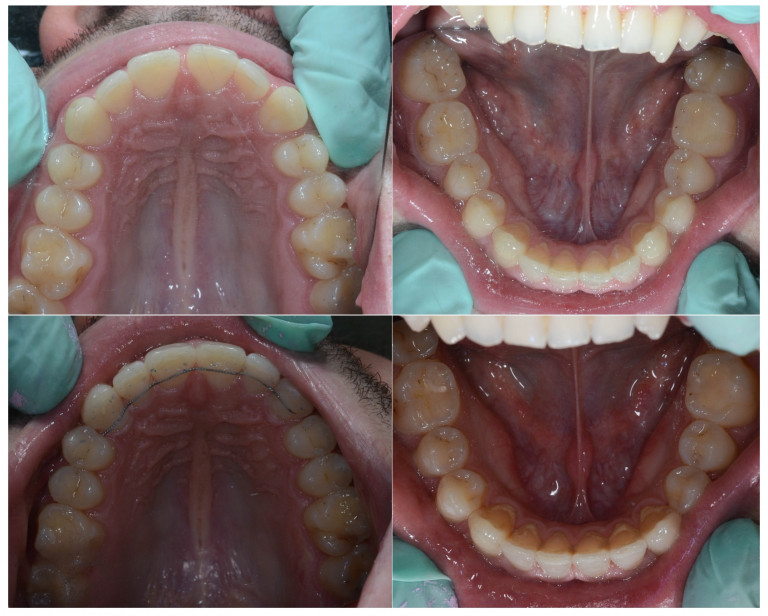

Slučaj 3: ispravljanje kompresije Invisalign full terapijom

Slučaj 4: ispravljanje kompresije Invisalign full terapijom

Slučaj 5: ispravljanje kompresije i križnog zagriza Invisalign full terapijom

Slučaj 6: ispravljanje kompresije i dubokog zagriza Invisalign full terapijom

Slučaj 7: ortodontska predprotetska terapija Invisalign full